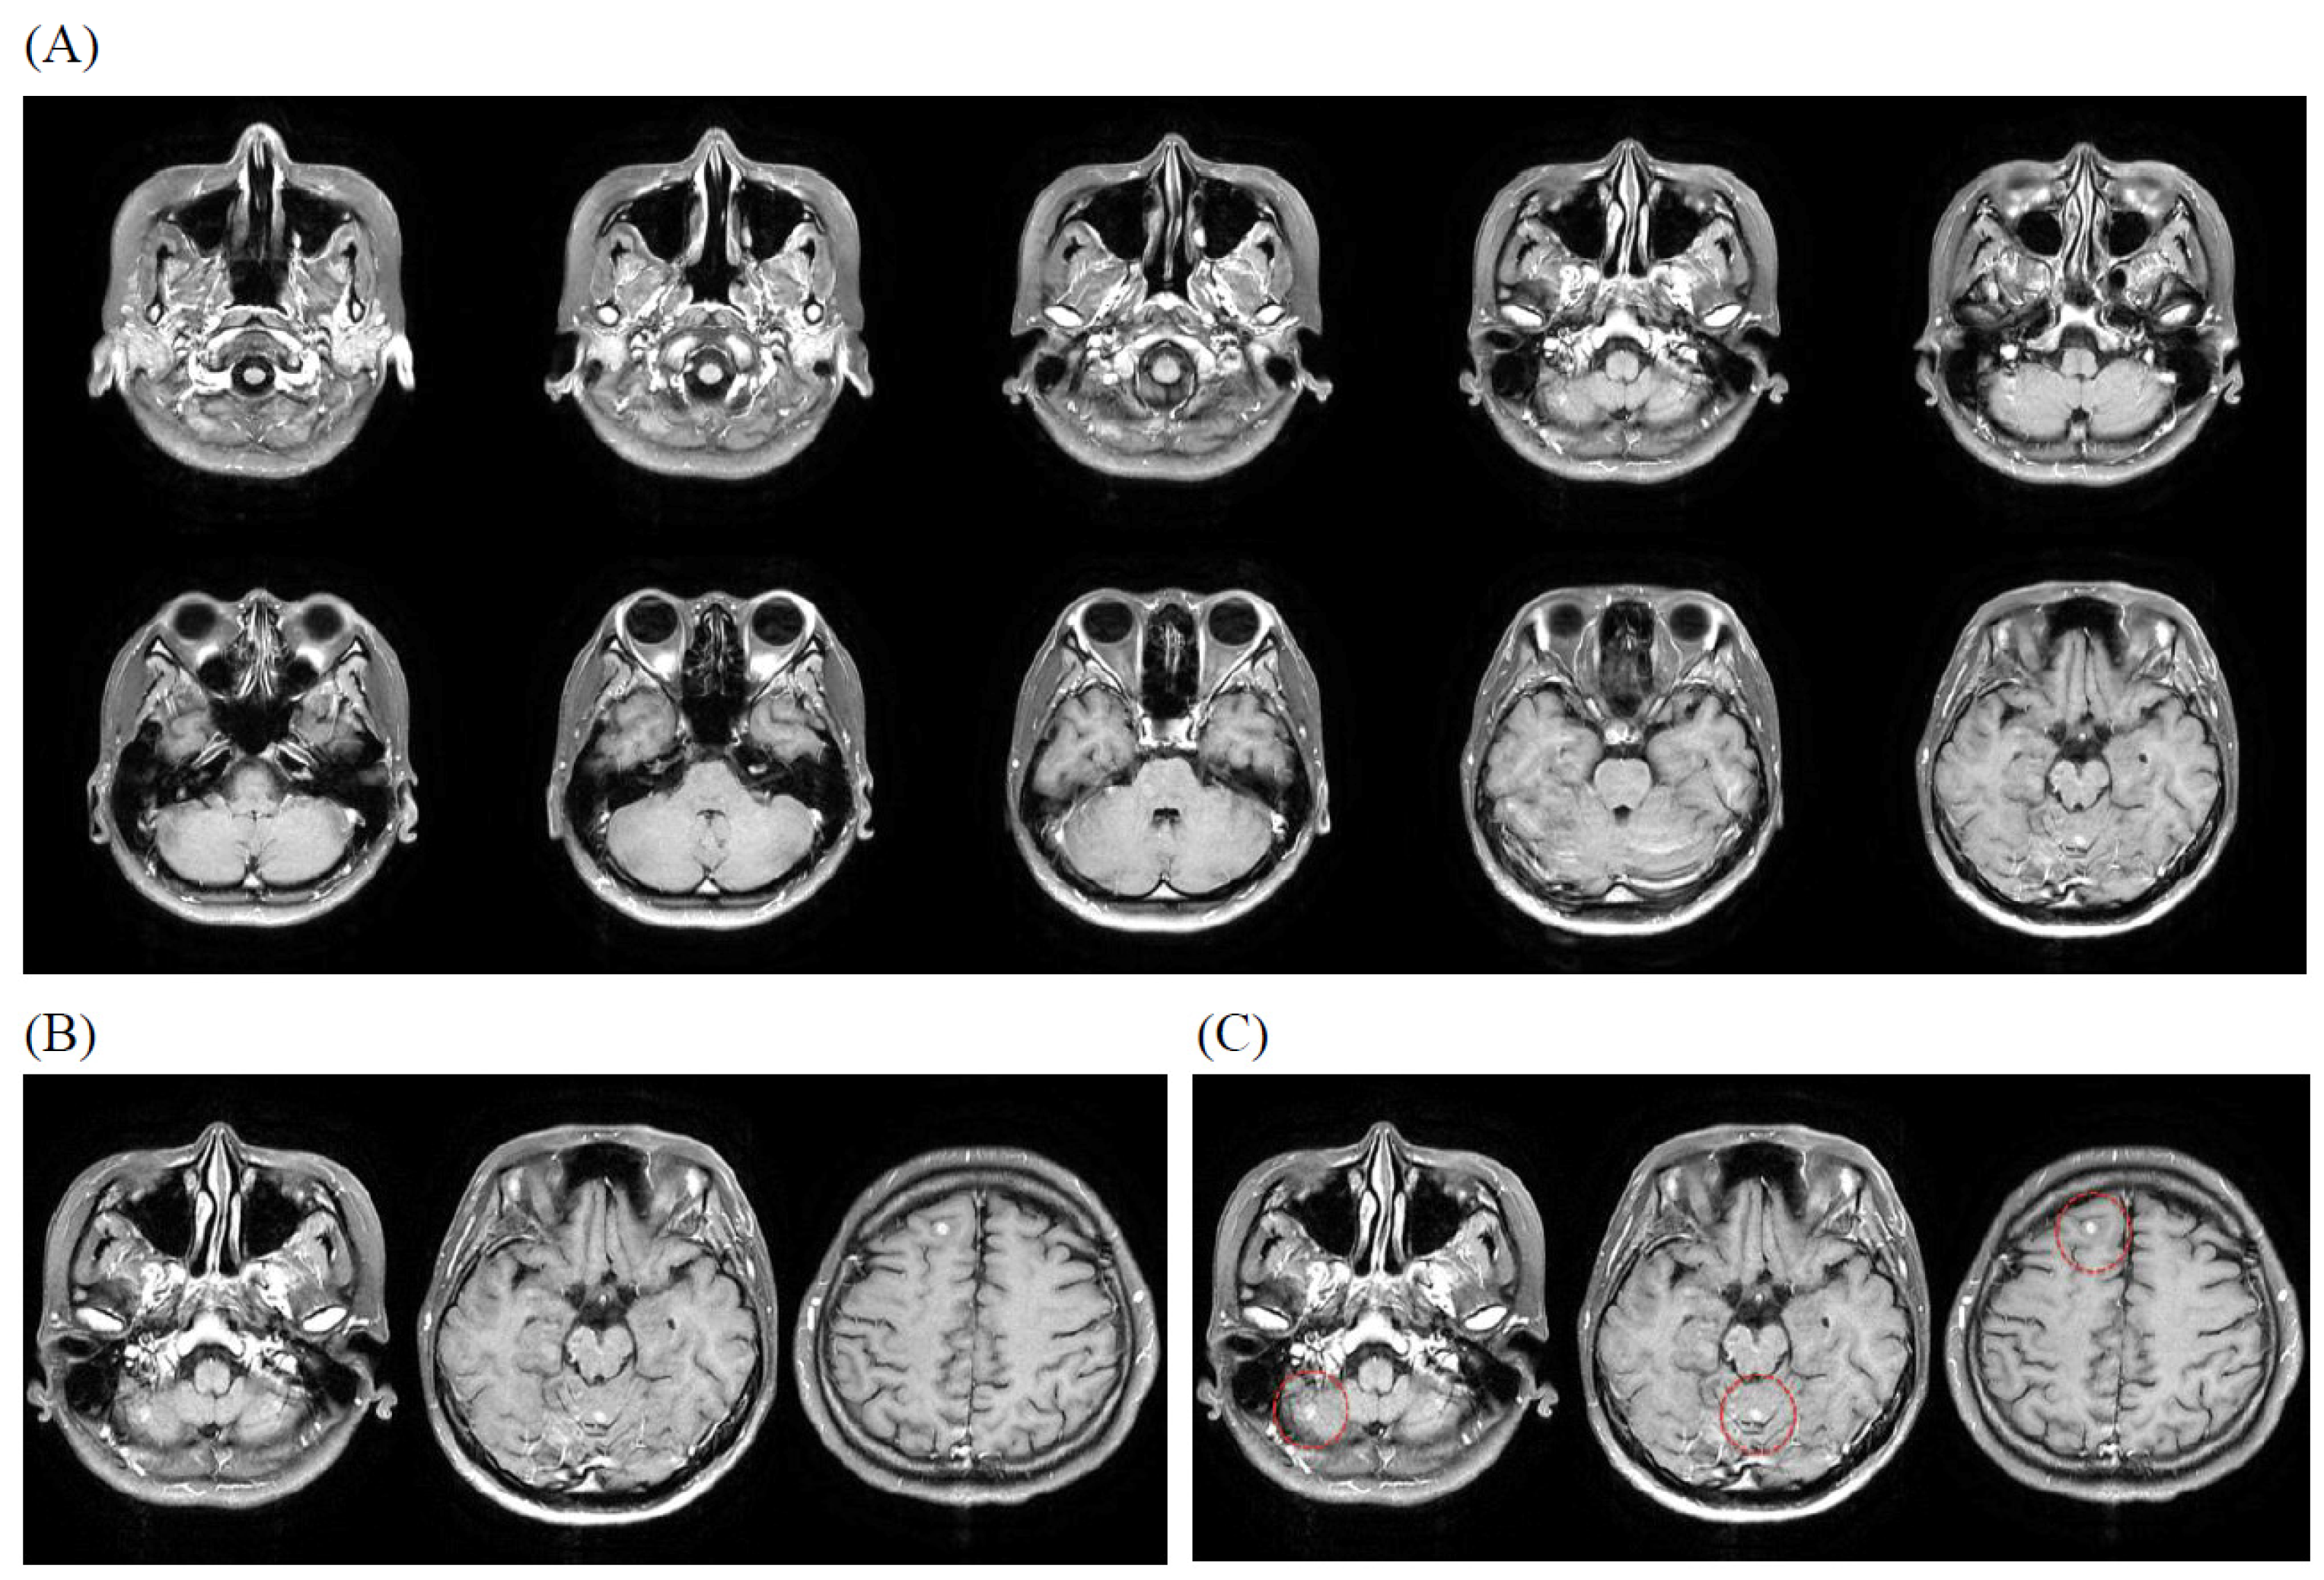

3.4. Illustrative Case